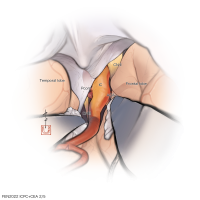

FEN2022シリーズ